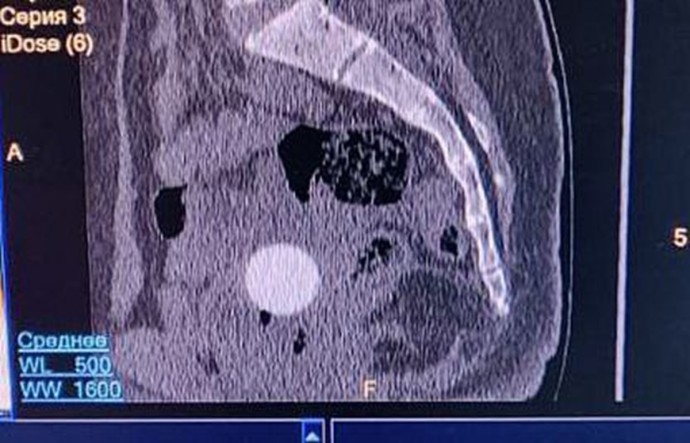

Родители обратились к врачу после того, как дочь начала жаловаться на периодические боли в области копчика. Компьютерная томография показала наличие инородного предмета в малом тазу. При осмотре выяснилось, что это был резиновый шарик.